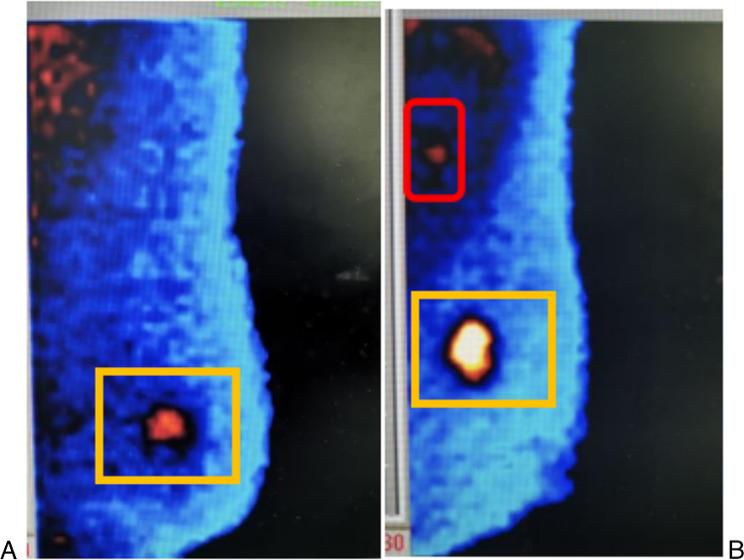

Cohorts of breast cancer patients who underwent surgery between 2012 and 2021 were created (The training set included 1104 ultrasound images and 940 BSGI images from 235 patients, the test set included 568 ultrasound images and 296 BSGI images from 99 patients) for the development of the prediction model. six machine learning (ML) methods and recursive feature elimination were trained in the training set to create a strong prediction model. Based on the best-performing model, we created an online calculator that can make a linear predictor in patients easily accessible to clinicians. The receiver operating characteristic (ROC) and calibration curve are used to verify the model performance respectively and evaluate the clinical effectiveness of the model.

Six ultrasonographic parameters (transverse diameter of tumour, longitudinal diameter of tumour, lymphatic echogenicity, transverse diameter of lymph nodes, longitudinal diameter of lymph nodes, lymphatic color Doppler flow imaging grade) and one BSGI features (axillary mass status) were selected based on the best-performing model. In the test set, the support vector machines' model showed the best predictive ability (AUC = 0.794, sensitivity = 0.641, specificity = 0.8, PPV = 0.676, NPV = 0.774 and accuracy = 0.737). An online calculator was established for clinicians to predict patients' risk of ALN metastasis ( https://wuqian.shinyapps.io/shinybsgi/ ). The result in ROC showed the model could benefit from incorporating BSGI feature.